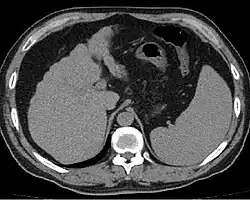

Диагностика

Расширенные и извитые венозные коллатерали выявляются при ангиографии, компьютерной томографии, ультразвуковом исследовании или в ходе оперативного вмешательства.